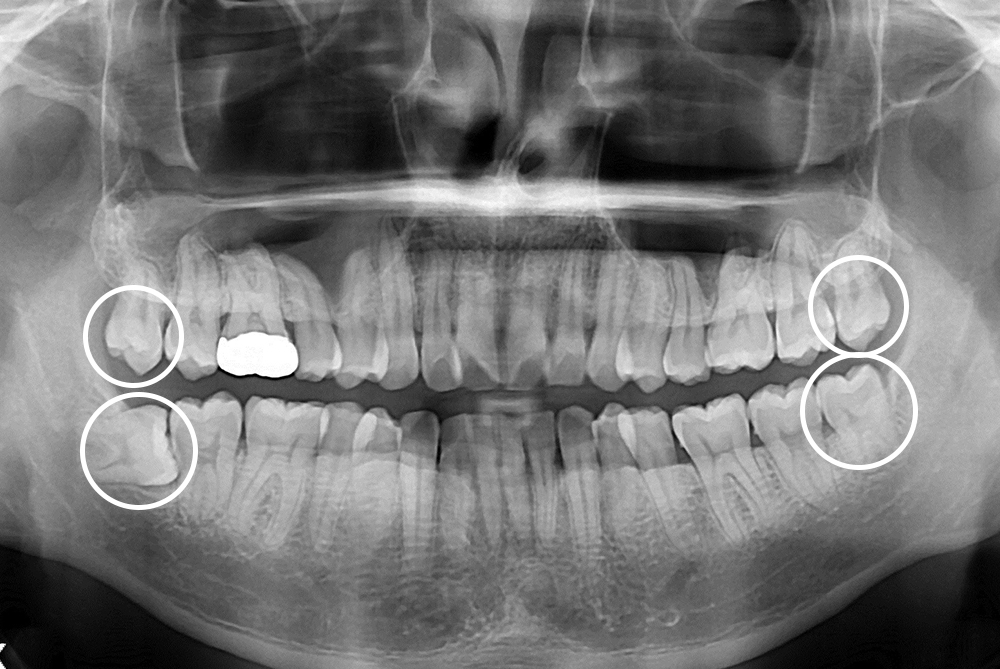

[사랑니] 매복 사랑니 발치

치료전 : 2016-12-21